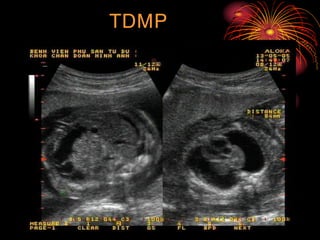

5- Hình aûnh sieâu aâm:

 Coù ít nhaát 3 trong 4 daáu sau: TDMB, TDMP, TDMNT, phuø

da

 TDMNT laø daáu hieäu ñaàu tieân

 Thöôøng xuyeân coù ña oái

 Baùnh nhau to vaø daøy leân

TDMNT: >= 2mm

TDMP